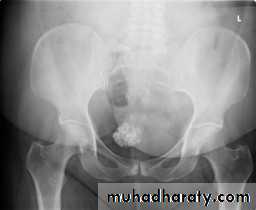

Calcifications: Fat may be deposited in fibroid which undergoes saponification. Co3 and Po4 in blood react with the soppy mass leading to deposition of CaCo3 and calcium phosphate

Grossly: It has a gritty appearance on cross section

A thin peripheral shell can be seen by X -ray